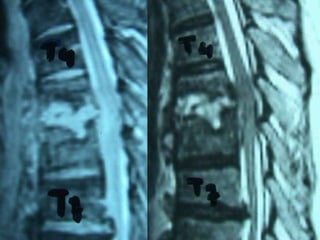

3rd case

EV. PY.

M 56 – Industrial labor

Symptoms

 Neurologic deficit

 Thoracic Pain

 Low fever

Laboratory

 Neutroph. ↑

 SR 45

Unknown Origin